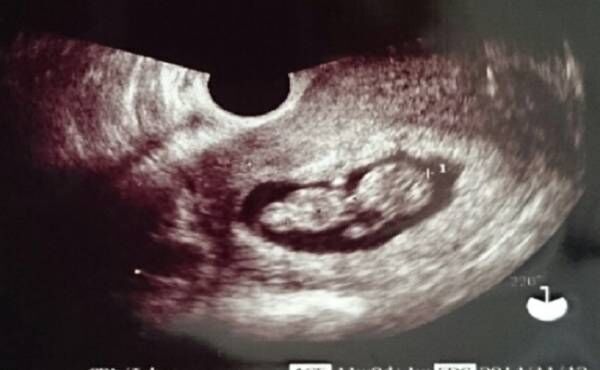

医師取材 妊娠中のエコー検査の種類と目的 先天障害はわかる Ameba News アメーバニュース

生まれてくる前の我が子の記念写真 超音波胎児スクリーニングでわかること 東京ベイ 浦安市川医療センター

正常がわかる胎児超音波検査 株式会社文光堂